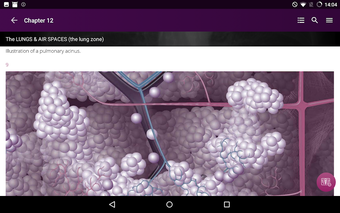

Radioloji'yi Keşfet: Göğüs Röntgeni Yorumlama, göğüs röntgeninin yorumlanmasının anlaşılmasını artırmak için tasarlanmış bir eğitim uygulamasıdır ve doktorlar, tıp öğrencileri ve radyologlar tarafından kullanılması amaçlanmaktadır. Uygulama, en küçük detayları görüntülemek için yakınlaştırılabilecek yüksek kaliteli görüntüler ve her bulgunun önemini anlamanıza yardımcı olacak bir sesli yorum içerir.

Uygulamanın amacı, kullanıcıların farklı x-ışını bulgularını ve bunların bir hastalığın teşhisinde nasıl kullanılabileceğini daha iyi anlamalarına yardımcı olmaktır. Uygulama, göğüs röntgeni yorumlaması için gerekli çeşitli yapı taşlarını kapsayan 5 bölüme ayrılmıştır.